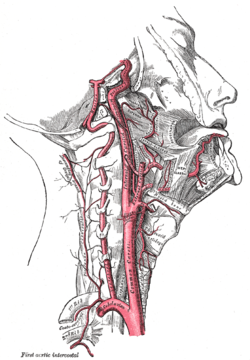

![]() شراين متفرعة من العنق. تتفرع الشرايين السباتية الغائرة من الشرايين السباتية الأصلية - موضحة على الشكل باسم Common caroti on the figure. | |

الشريان السباتي الغائر، يقع على الجانب الداخلي من العنق على الجانب المقابل للشريان السباتي الظاهر.[1] في التشريح البشري، تتفرع الشرايين السباتية الغائرة من الشرايين السباتية الأصلية حيث تتشعب هذه الشرايين السباتية الغائرة والظاهرية عند مستوى الفقرة العنقية 3 أو 4؛ يوصل الشريان السباتي الغائر الدم للمخ بما في ذلك العينين،[2] بينما يوصل الشريان السباتي الظاهري الدم لمناطق أخرى في الرأس، مثل الوجه، فروة الرأس، الجمجمة، والسحايا.